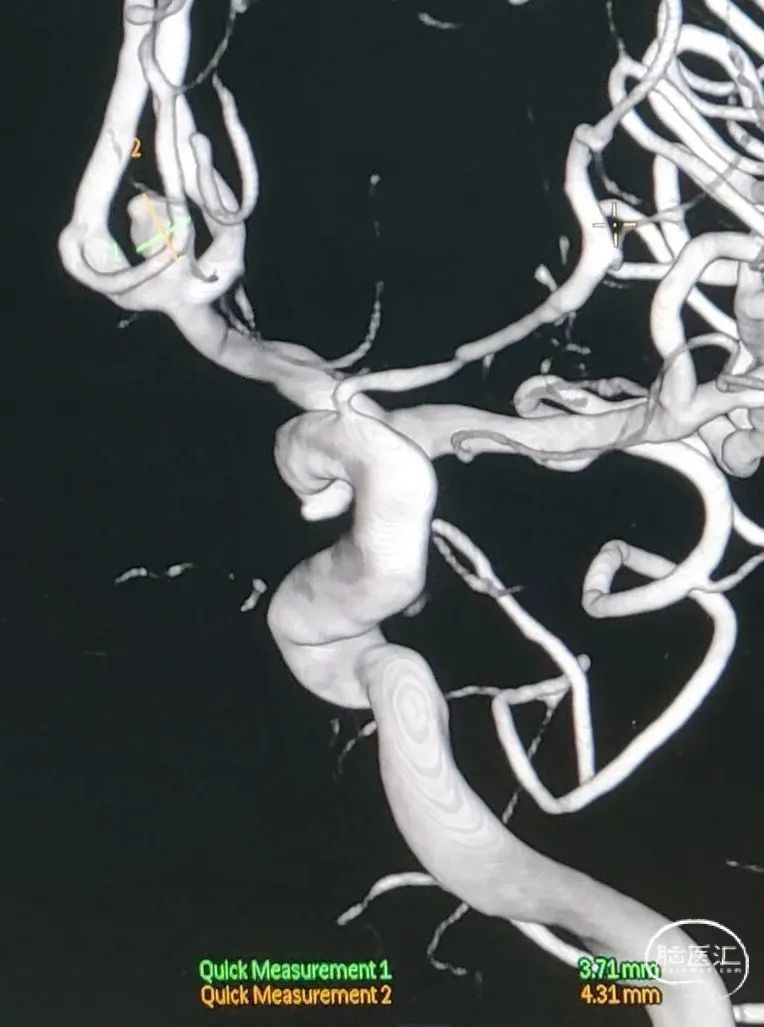

分叶状前交通宽颈动脉瘤

动脉瘤呈分叶状,瘤顶及瘤颈处见3个子囊。

动脉瘤测量:

动脉瘤特点:

术前影像